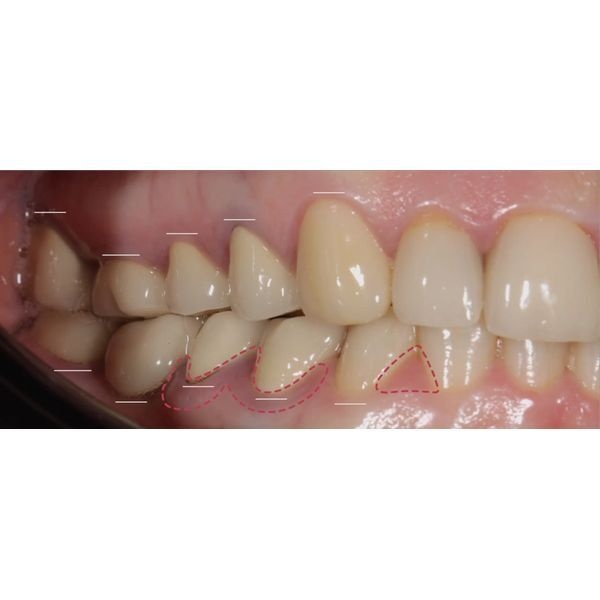

При осмотре выяснилось, что конструкции на центральных зубах хоть и выглядели эстетично, на них появились трещины и сколы, было нарушено краевое прилегание. Кроме того, у женщины наблюдалась стираемость зубов, особенно заметно стёрся нижний клык (зуб 3.3). На других зубах также присутствовали сколы.

Жевательные поверхности боковых зубов оставались гладкими. Это говорило о том, что у пациентки не было окклюзионных помех, которые могли бы спровоцировать проблемы с височно-нижнечелюстным суставом (ВНЧС), однако из-за отсутствия рельефа контакт между зубами-антагонистами плоскостной, а не точечный, поэтому мышцам приходилось прилагать больше усилий, чтобы пережевать пищу.

- создать пространство для моделирования боковых стёртых зубов.